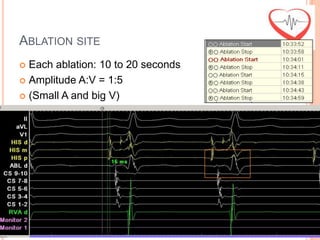

ABLATION SITE

 Amplitude A:V = 1:5

 (Small A and big V)

 Each ablation: 10 to 20 seconds

ABLATION SITE  AmplitudeA:V = 1:5  (Small A and big V)  Each ablation: 10 to 20 seconds

ABLATION SITE  Eachablation: 10 to 20 seconds  Amplitude A:V = 1:5  (Small A and big V)